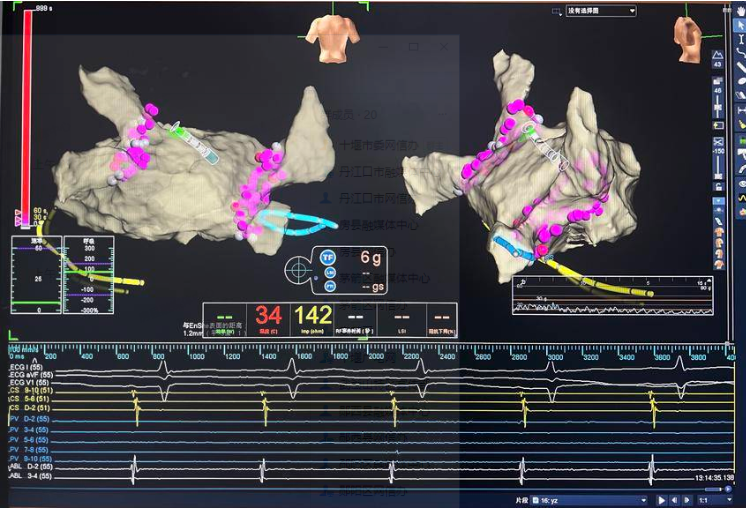

消融圖片

手術(shù)當(dāng)日,范群雄副主任醫(yī)師、趙繼先主任醫(yī)師領(lǐng)銜的手術(shù)團(tuán)隊嚴(yán)陣以待。此次手術(shù),穿刺環(huán)節(jié)是關(guān)鍵和難點。由于卵圓孔封堵器的存在,穿刺路徑受到了極大的限制。為了克服這一困難,手術(shù)團(tuán)隊采取了多項措施,確保手術(shù)安全、順利。首先,他們利用DSA(數(shù)字減影血管造影)和三維心臟建模技術(shù),對朱女士的心臟結(jié)構(gòu)進(jìn)行了精確的分析,使得手術(shù)團(tuán)隊能夠清晰地看到房間隔、卵圓孔封堵器以及周圍血管的位置關(guān)系,從而制定出更加精準(zhǔn)的穿刺路徑。其次,手術(shù)團(tuán)隊在穿刺過程中,小心翼翼地操控穿刺針,通過精準(zhǔn)把控力度和角度,在復(fù)雜的心臟結(jié)構(gòu)中準(zhǔn)確地找到穿刺點,并避免對周圍組織的損傷。

隨后,手術(shù)團(tuán)隊乘勝追擊,運用射頻消融技術(shù)進(jìn)行了雙側(cè)肺靜脈前庭及上腔靜脈電隔離,精準(zhǔn)地消除了房顫病灶,恢復(fù)了心臟的正常節(jié)律。緊接著,手術(shù)團(tuán)隊將左心耳封堵器放置到位,鉤掛穩(wěn)定。造影顯示,左心耳封堵完好,未見明顯殘余漏。這一步驟的成功,徹底阻斷了血栓形成的源頭,為朱女士的未來生活提供了有力的保障。